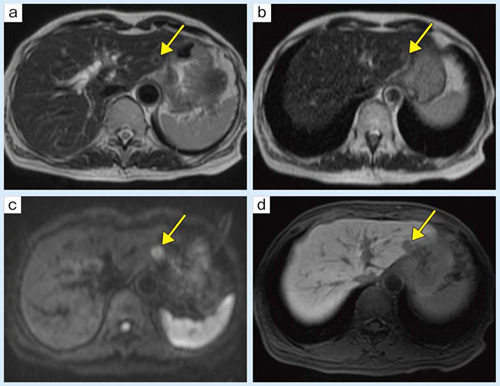

■症例1:直腸がん術後

肝S5にT2強調像で高信号域を認める(a ↓)。Gd-EOB-DTPA造影MRI肝細胞相(d ↓)では周囲より低信号である。これだけでは転移と嚢胞の鑑別は難しいが,Heavy T2強調像で強い高信号(b ↓),FLAIRで低信号となり(c ↓),転移ではなく嚢胞であることがわかる。同様の嚢胞が肝左葉外側区にも見られている(b ▼)。

a:T2 WI,FOV:370mm,TR/TE:3000/100,FA:90°,スライス厚:7mm

b:Heavy T2 WI,FOV:370mm,TR/TE:13000/100,FA:90°,スライス厚:7mm

c:FLAIR,FOV:370mm,TR/TE/TI:13000/100/2200,FA:90°,スライス厚:7mm

d:Gd-EOB-DTPA造影MRI肝細胞相,FOV:370mm,TR/TE:4.3/1.8,FA:12°,スライス厚:3mm

■症例2:上行結腸がん術後

肝左葉外側区にT2強調像でリング状の高信号域が見られる(a ↓)。この病変は,Gd-EOB-DTPA造影MRI肝細胞相で周囲より低信号である(d ↓)。しかし,FLAIRで淡い高信号(b ↓),拡散強調像でも高信号(c ↓)となり,転移が疑われる。本症例は手術が施行され,病理検査で転移と診断された。

b:FLAIR,FOV:370mm,TR/TE/TI:13000/100/2200,FA:90°,スライス厚:7mm

c:DWI,FOV:370mm,TR/TE:3000/52,FA:90°,b値:500,スライス厚:7mm